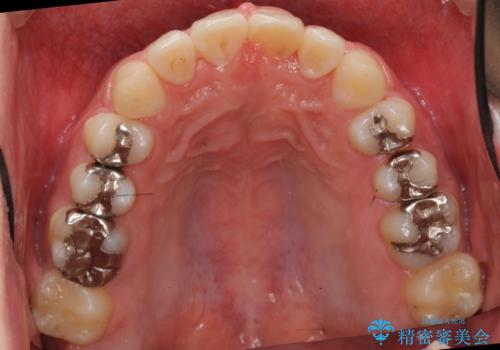

- 前歯のねじれを部分矯正で治療しました。

奥歯のかみ合わせを変えずに、費用を抑えて短期間に治療したい方におすすめです。

奥歯のかみあわせも問題なく、また、下の前歯のがたつきが元からない場合は上の部分矯正が十分可能です。